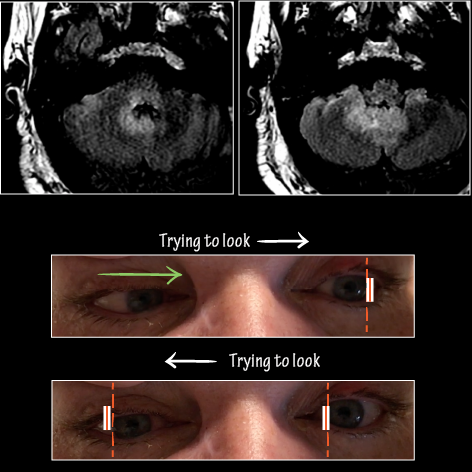

Patient presents with diplopia, vertigo, and incoordination. Exam reveals profound horizontal eye movement abnormalities and right side ataxia.

• MRI imaging demonstrates significant pontine inflammation and right cerebellar inflammation.